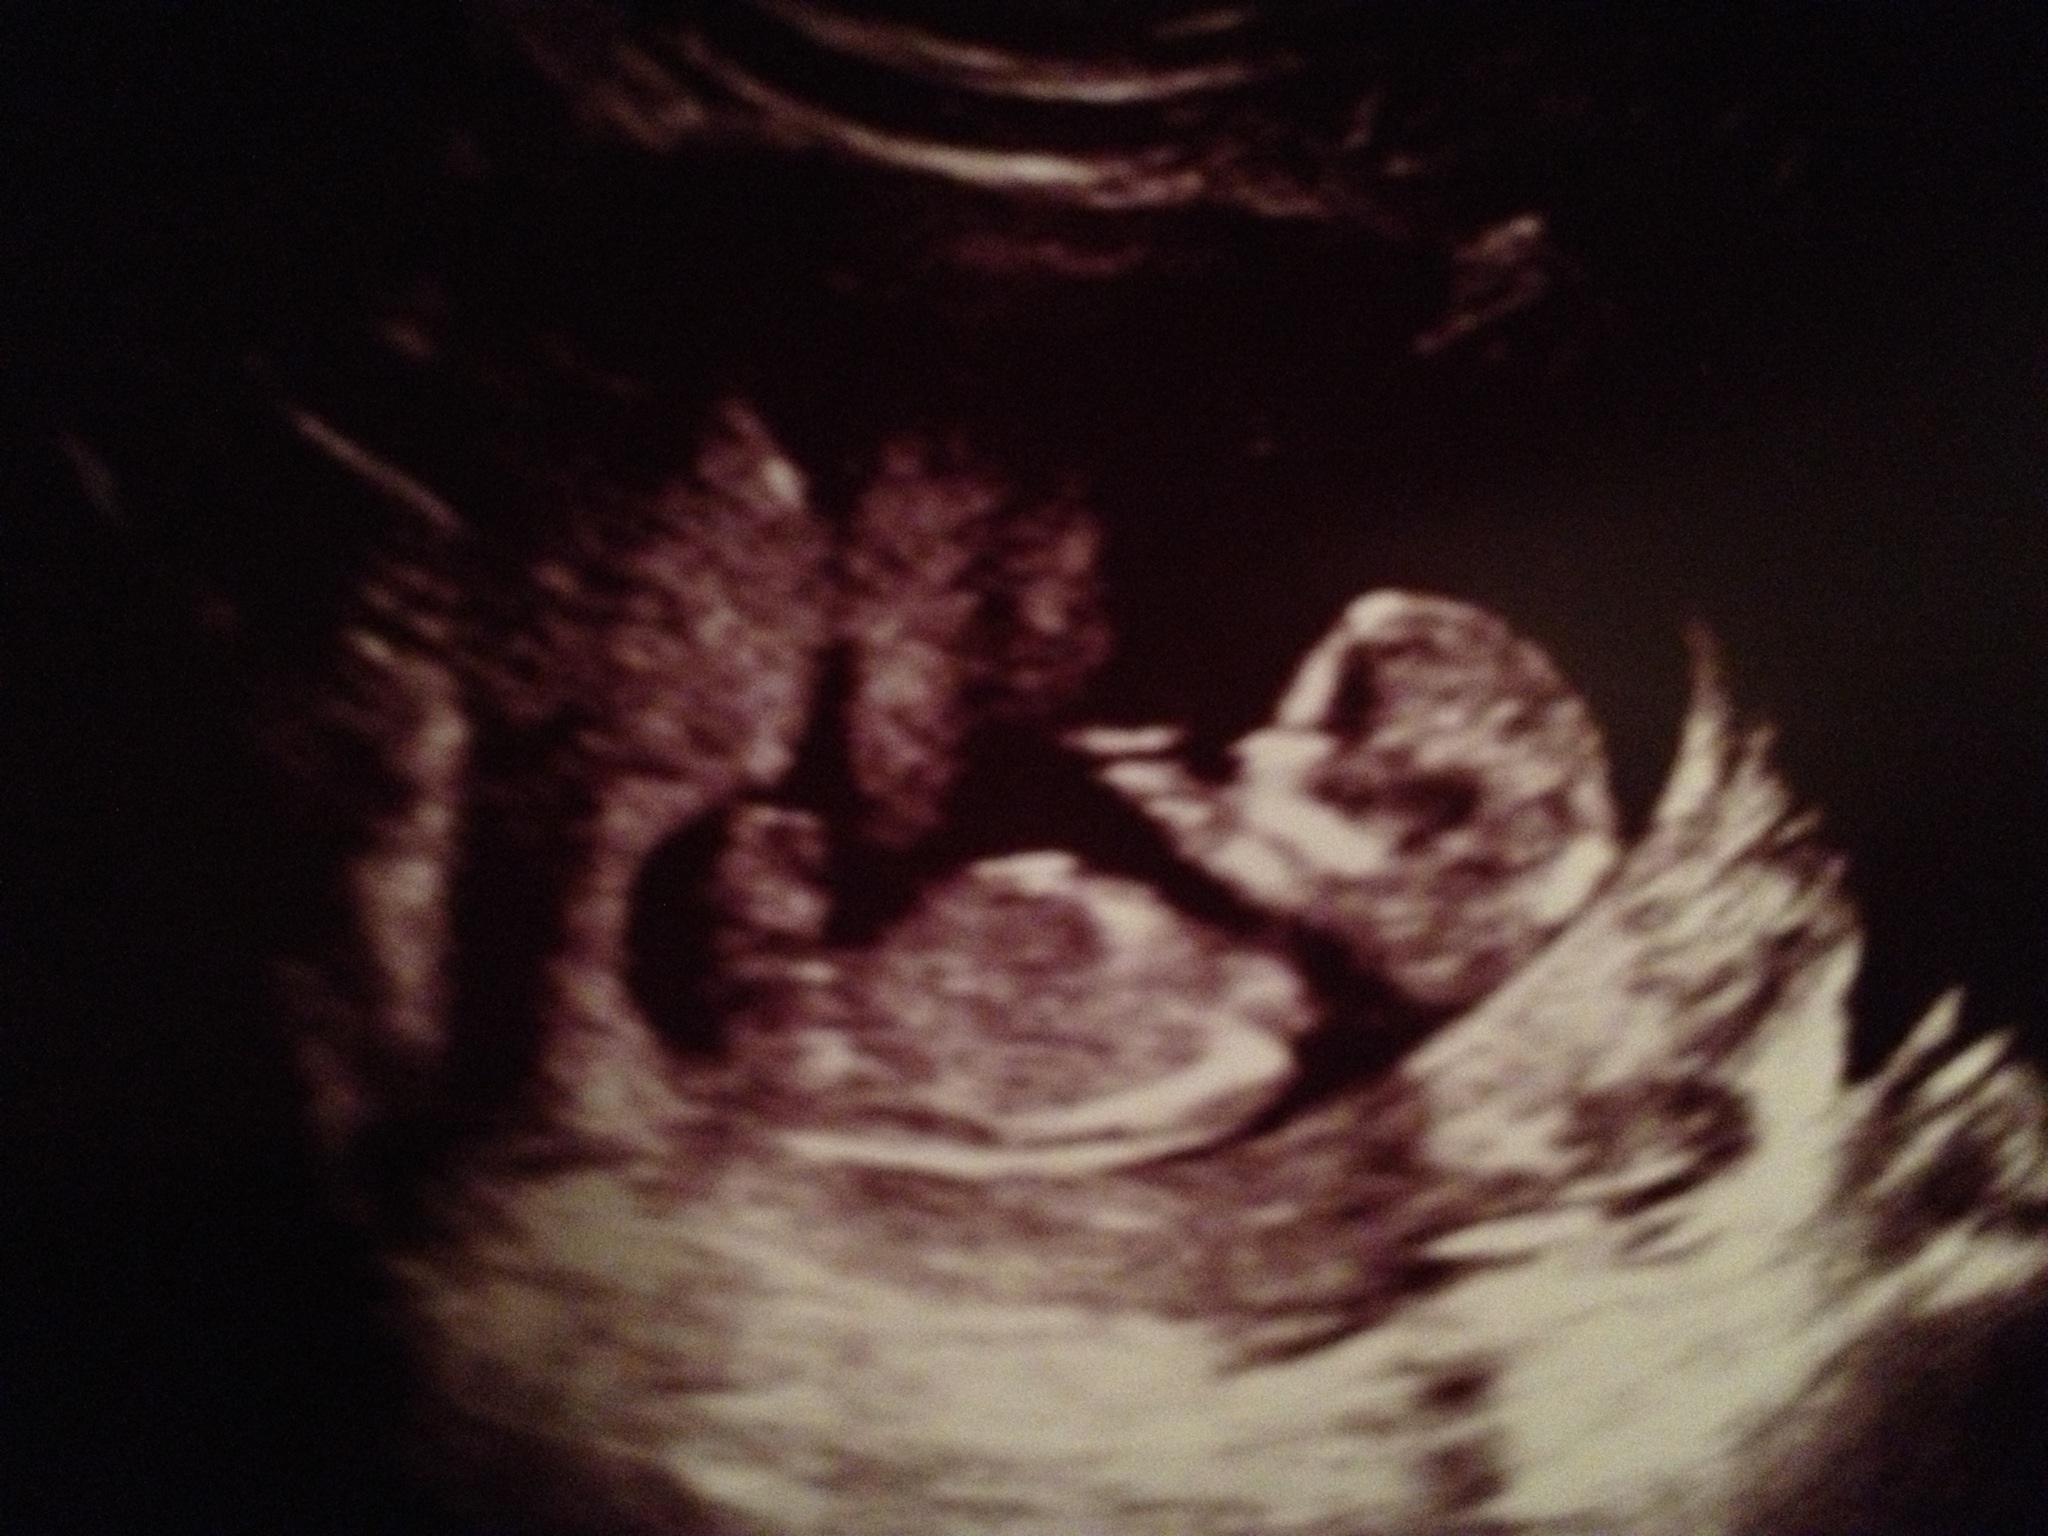

Hi everyone! We are expecting our second child in Feb 2014. Here are my ultrasound pics from today...12 weeks 5 days. I believe there is a nub on 1st and 2nd pic. Can you please guess boy or girl based on nub and/or skull? Thanks so much for your predictions!!